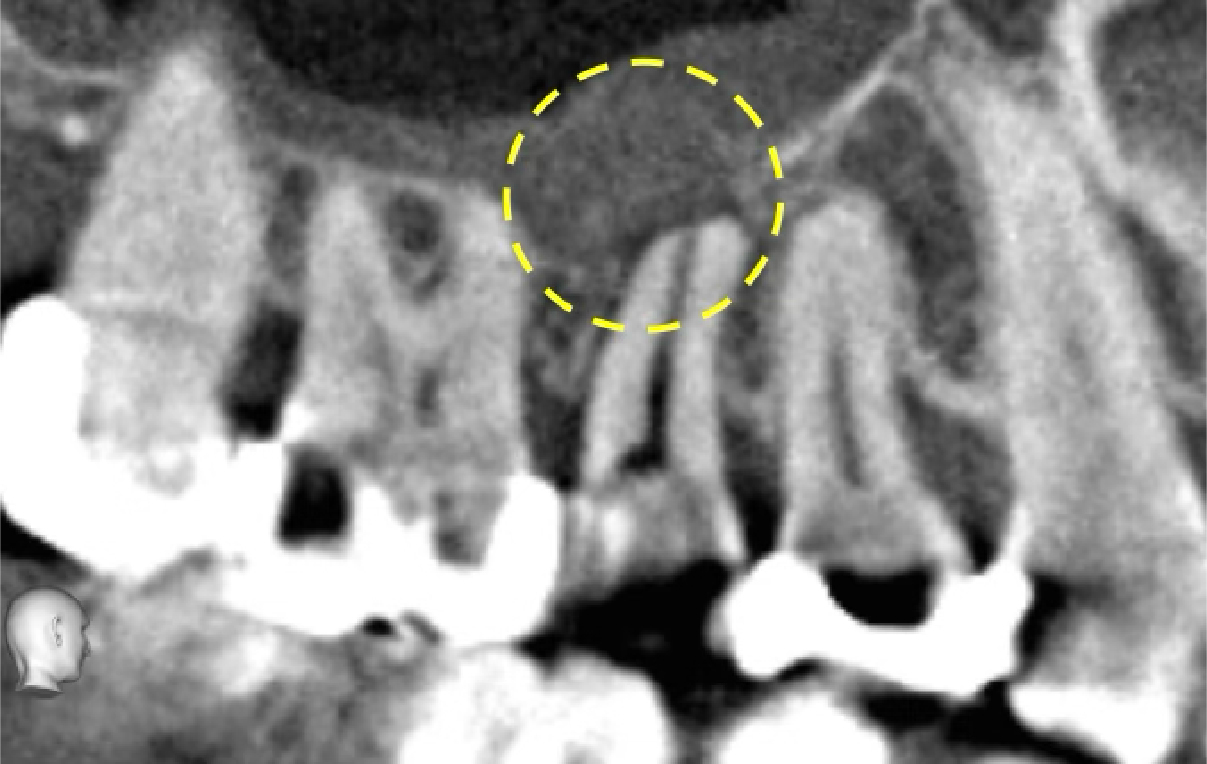

術後、3、6、12ヶ月の経過観察を行いました。6ヶ月時点では根尖部の透過像は残っていましたが、12ヶ月時点で根尖部の骨吸収像は消失し、良好な経過をたどっています。

歯茎の腫れ(フォステル)も、術後6ヶ月時点で消失しました。

今後、さらに長期にわたり、骨組織はより成熟していくことが予想されます。